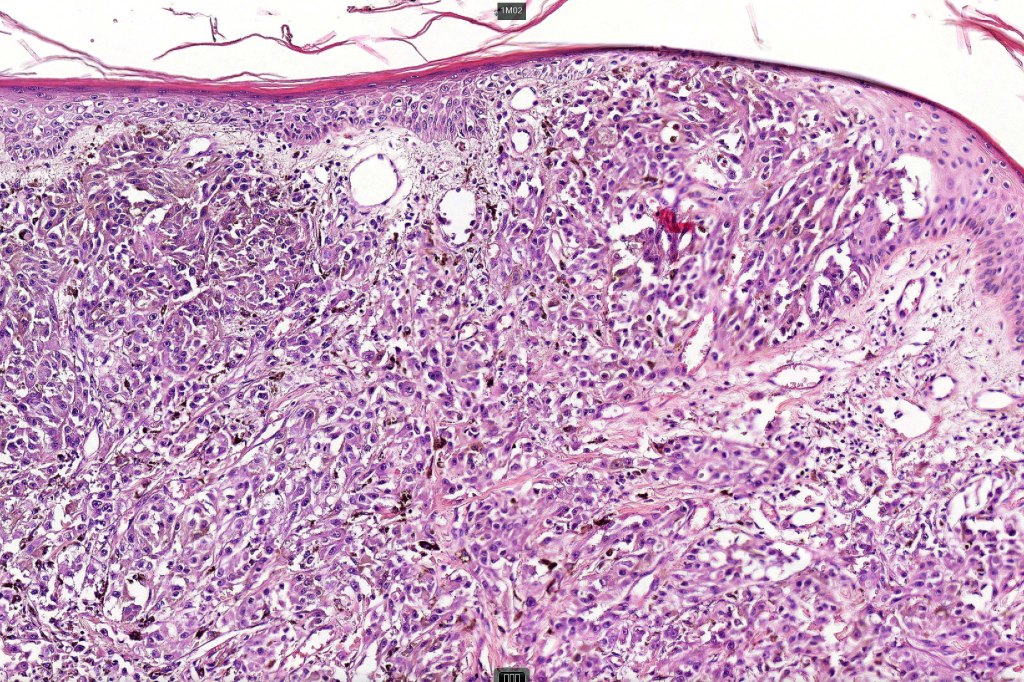

Histological features

•Develops within a precursor lesion as one or more nodules of epithelioid or spindled cell melanoma

•Nuclear pleomorphism with prominent nucleoli, mitotic activity & abnormal mitoses

•Necrosis sometimes present

•Occasionally perineural infiltration or vascular invasion seen